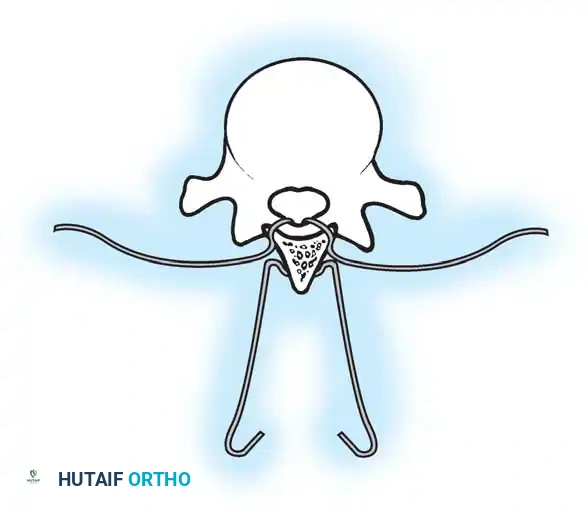

The Moe Technique (Thoracic Spine)

The Moe technique is a highly effective method for achieving intra-articular arthrodesis in the coronally oriented thoracic facet joints.

Fig. 38-26: The Moe technique of thoracic facet fusion, demonstrating the creation of hinged bone flaps.

- Expose the spine fully to the tips of the transverse processes.

- Using a sharp osteotome or Cobb gouge, begin a cut over the cephalad articular process at the base of the lamina.

- Carry this cut along the transverse process almost to its tip. Bend this cortical fragment laterally so it lies between the transverse processes, ideally leaving it hinged on its lateral periosteal attachment to preserve local vascularity.

- Thoroughly denude all articular cartilage from the superior articular process using a sharp curet.

- Make a secondary cut in the superior articular facet, working medially to laterally, producing another hinged fragment.

- Pack the resulting intra-articular defect tightly with cancellous bone graft.